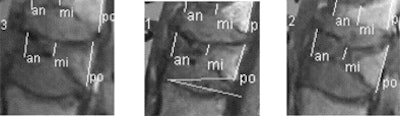

| Preoperative MRI (above) and postoperative CT (below) show growth in vertebral height before and after vertebroplasty, measured at anterior border (an), medial (mi), and posterior border (po) of the vertebral body at right (image at left), middle (middle), and left (image at right) for both modalities. Compared to control subjects, postprocedural mean height of treated vertebrae increased significantly (p < 0.001) from 4% to 38% of initial height, after vertebroplasty for an overall increase of 0.1-1.5 cm, median value 0.16-0.27 cm. All images courtesy of Dr. Johannes Hierholzer. |

"We chose nine points -- at the posterior border, anterior border, and middle of the vertebral body," Hierholzer said. Following the normal clinical protocol at his facility, different imaging modalities were used before and after the procedure.

"We had to compare MRI preop with CT reformatted images postop ... with the three MRIs: medial, left, and right sagittal plane, and the corresponding CT slices plus (assessment of) the kyphotic angle," Hierholzer said. The measurement method was validated with the comparison of control imaging data from the same nine data points in untreated vertebral bodies.